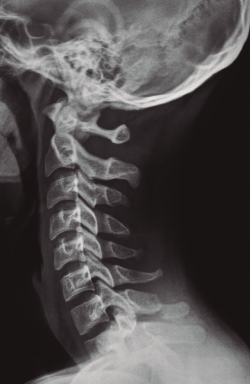

Figura 1. Fractura de la apófisis espinosa de C7.

Se solicitó estudio radiográfico(3) y tomografía computarizada (TC)(4) de la columna cervical donde se apreció una fractura con ligera desviación de fragmentos de la apófisis espinosa de C7 (Figuras 1 y 2).